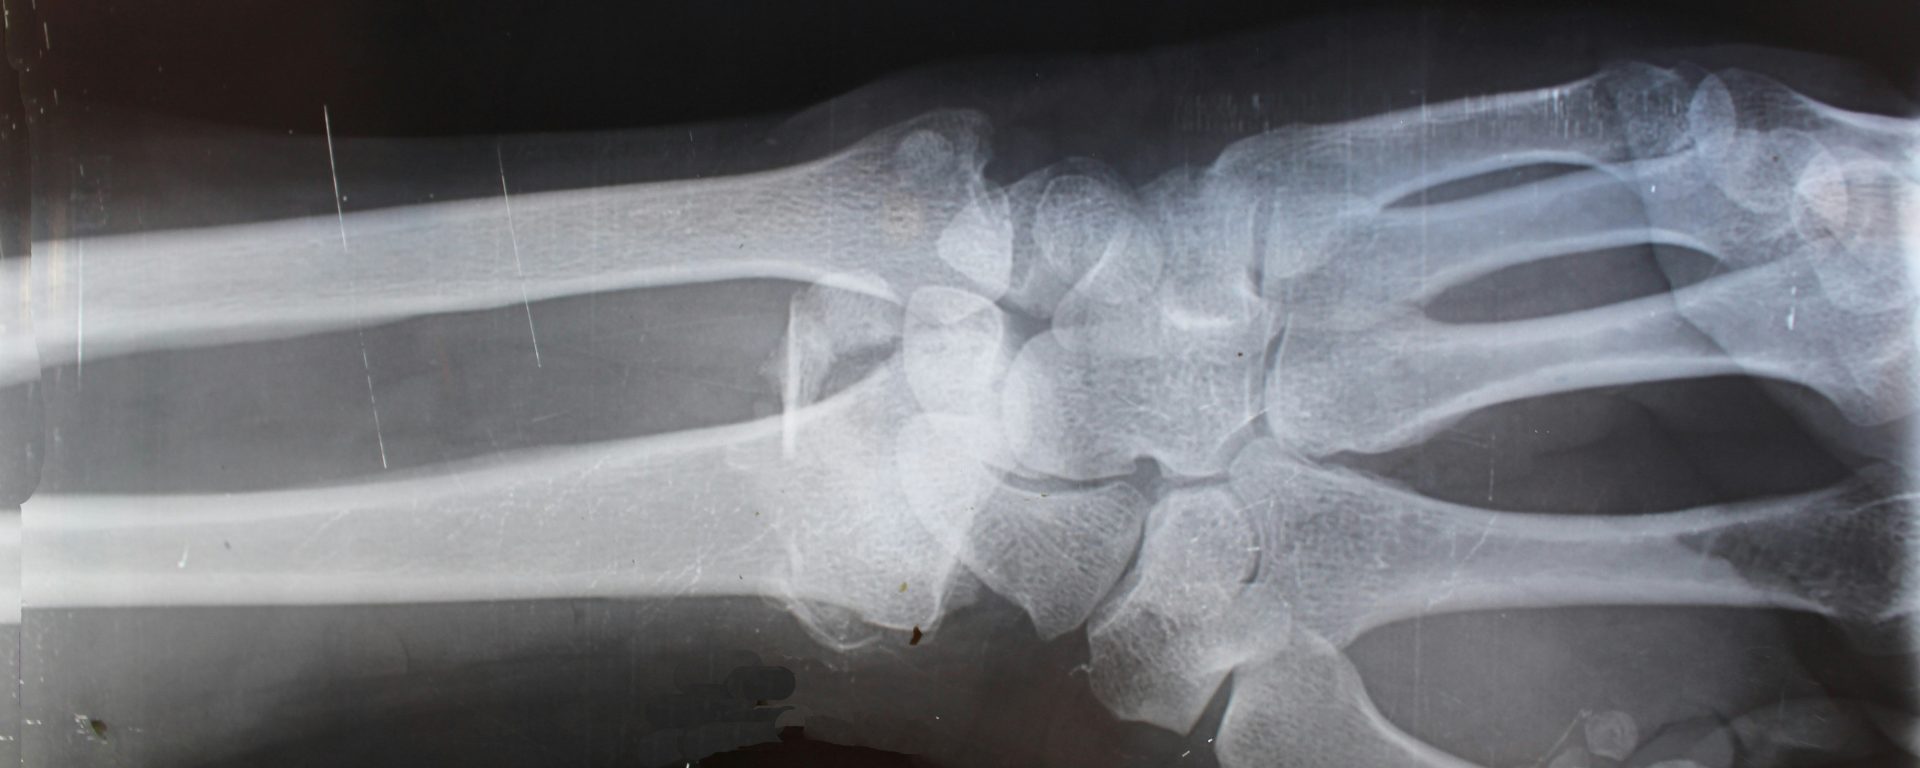

放射技术专家主要负责设置和操作专门的成像设备,包括x射线技术、磁共振成像(MRI)扫描仪和计算机断层扫描(CT)机器。 放射技术专家使用这些技术来创建患者身体(或关注区域)的图像,然后用于诊断和治疗疾病。

- 进行医学成像 使用先进的设备,如核磁共振、CT机、超声波、透视设备等

- 评价图像 与内科医生或放射科医生确认诊断是否需要更多的影像学检查

- 解释图片 与医疗团队合作,帮助供应商识别异常情况并生成/开发报告